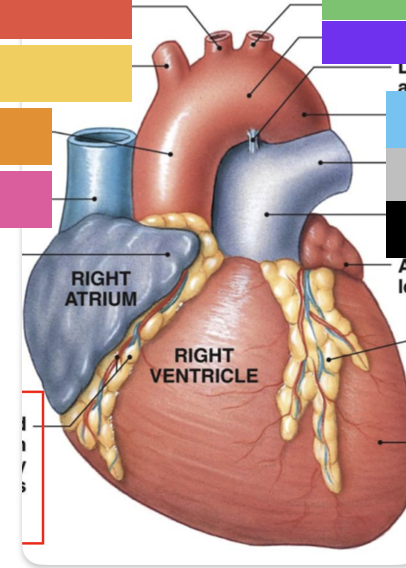

right atrium

right auricle

right ventricle

interatrial septum

interventricular septum

anterior interventricular sulcus

superior vena cava

inferior vena cava

pulmonary trunk

right coronary artery